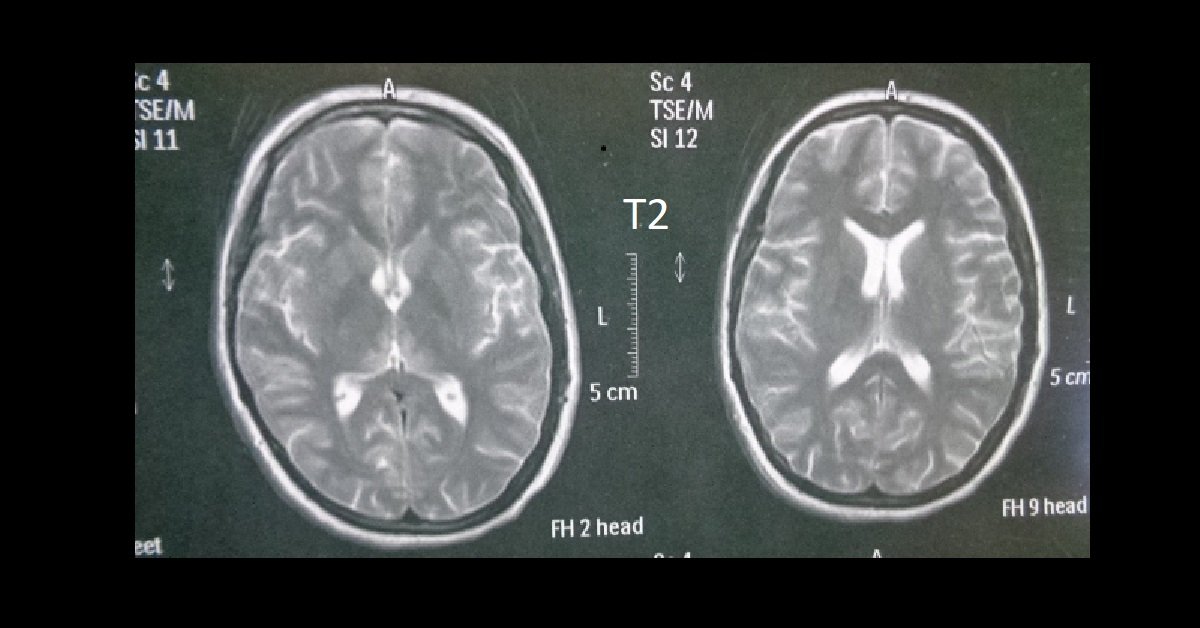

Wernicke's Encephalopathy, MRI Stock Image Science Source Images Hand Flapping Encephalopathy Learn about the possible causes, such as liver or kidney diseases, how to. Flapping hand tremors, or asterixis, are involuntary jerking movements of the hands caused by brain damage. Asterixis is a neurological disorder that causes involuntary flapping movements of the hands, fingers, and wrists. Uremic encephalopathy can present with intermittent loss of muscular tone in an outstretched arm, known. Hand Flapping Encephalopathy.

Wernicke's Encephalopathy, MRI Stock Image C036/5258 Science Hand Flapping Encephalopathy Learn about the possible causes, such as liver or kidney diseases, how to. Uremic encephalopathy can present with intermittent loss of muscular tone in an outstretched arm, known as asterixis. If the patient cannot extend the knee, it may be held in a flexed position. A flap at the ankle joint or brief quick leg lowering indicates a positive asterixis.. Hand Flapping Encephalopathy.